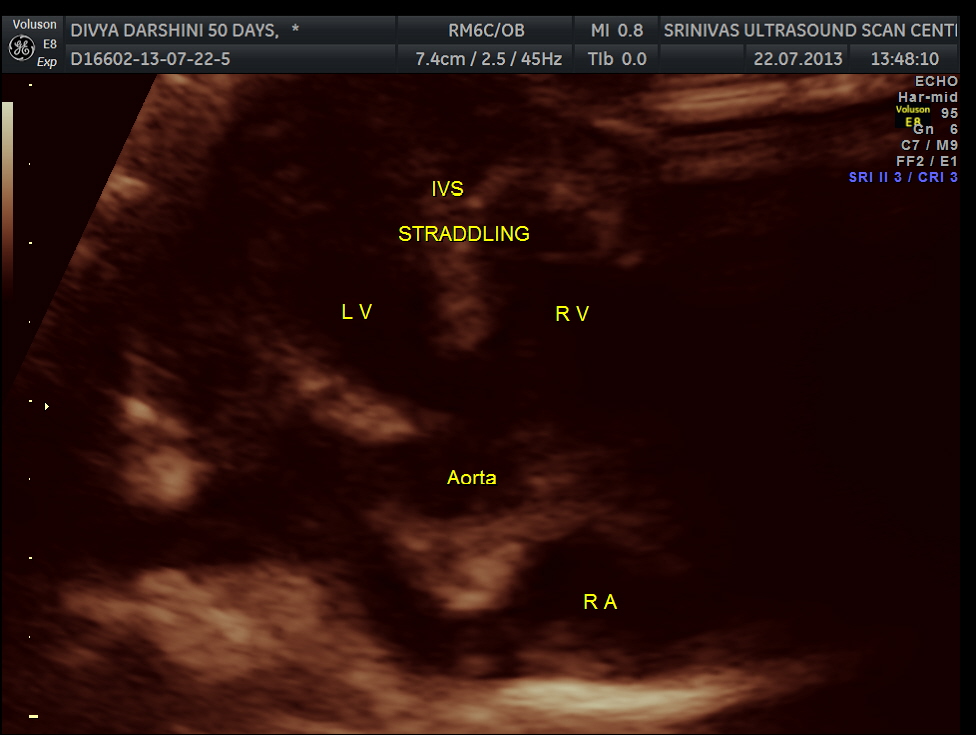

The following pictures are of the heart of the child .

The IVS straddling the aorta is prominently seen ; The RV is mildly dilated . Though the pulmonary artery was difficult to comment on , I would still go with TETRALOGY OF FALLOT with RENAL DYSPLASIA , which makes it complicated.